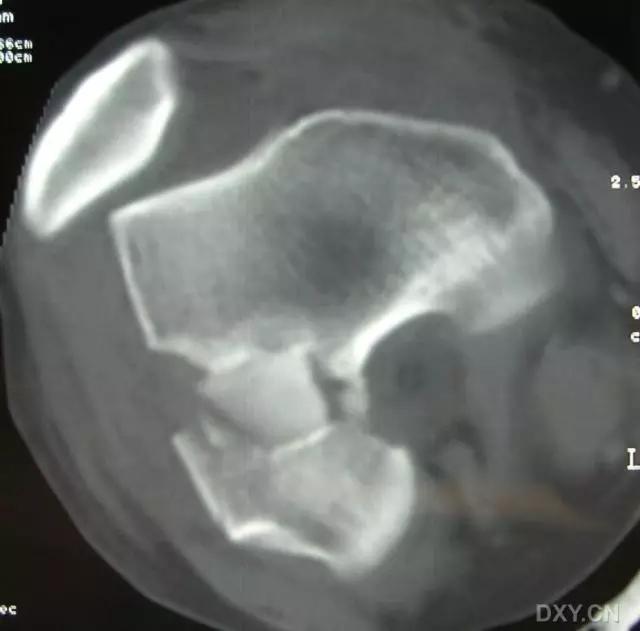

5. Hoffa 骨折

指股骨远端冠状面的骨折。

病例 1:一般股骨髁间、髁上粉碎骨折中含 Hoffa 骨折的不少见,但单纯后髁骨折则很少见。

水平位 CT